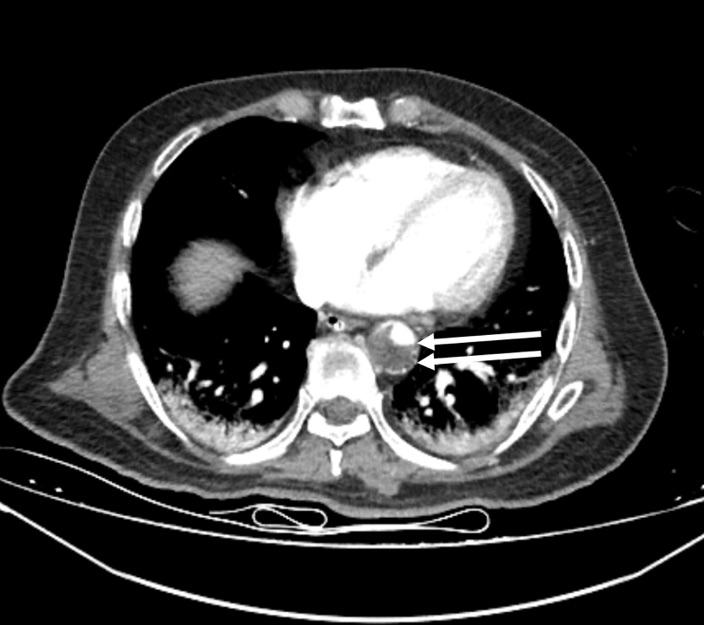

On the 13th day, the left foot was noted to be cold and ischemic, with the posterior tibial pulse not palpable. Similarly, the left hand was cold, and the radial pulse was absent. Arterial thrombosis was suspected, and Doppler ultrasonography confirmed thrombosis in the posterior tibial artery. A contrast-enhanced CT angiogram (Figure 1-3) revealed arterial thrombosis extending downward from the descending aorta, a splenic subcapsular ischemic appearance, arterial thrombosis narrowing the lumen in the left iliac and femoral arteries, and posterior tibial artery occlusion in the left leg. The patient was managed medically without surgical intervention, pentoxifylline 1500 mg/24 h infusion, dipyridamole 75 mg 1x1 tablet was started, and enoxaparin was increased to 60 mg twice daily.